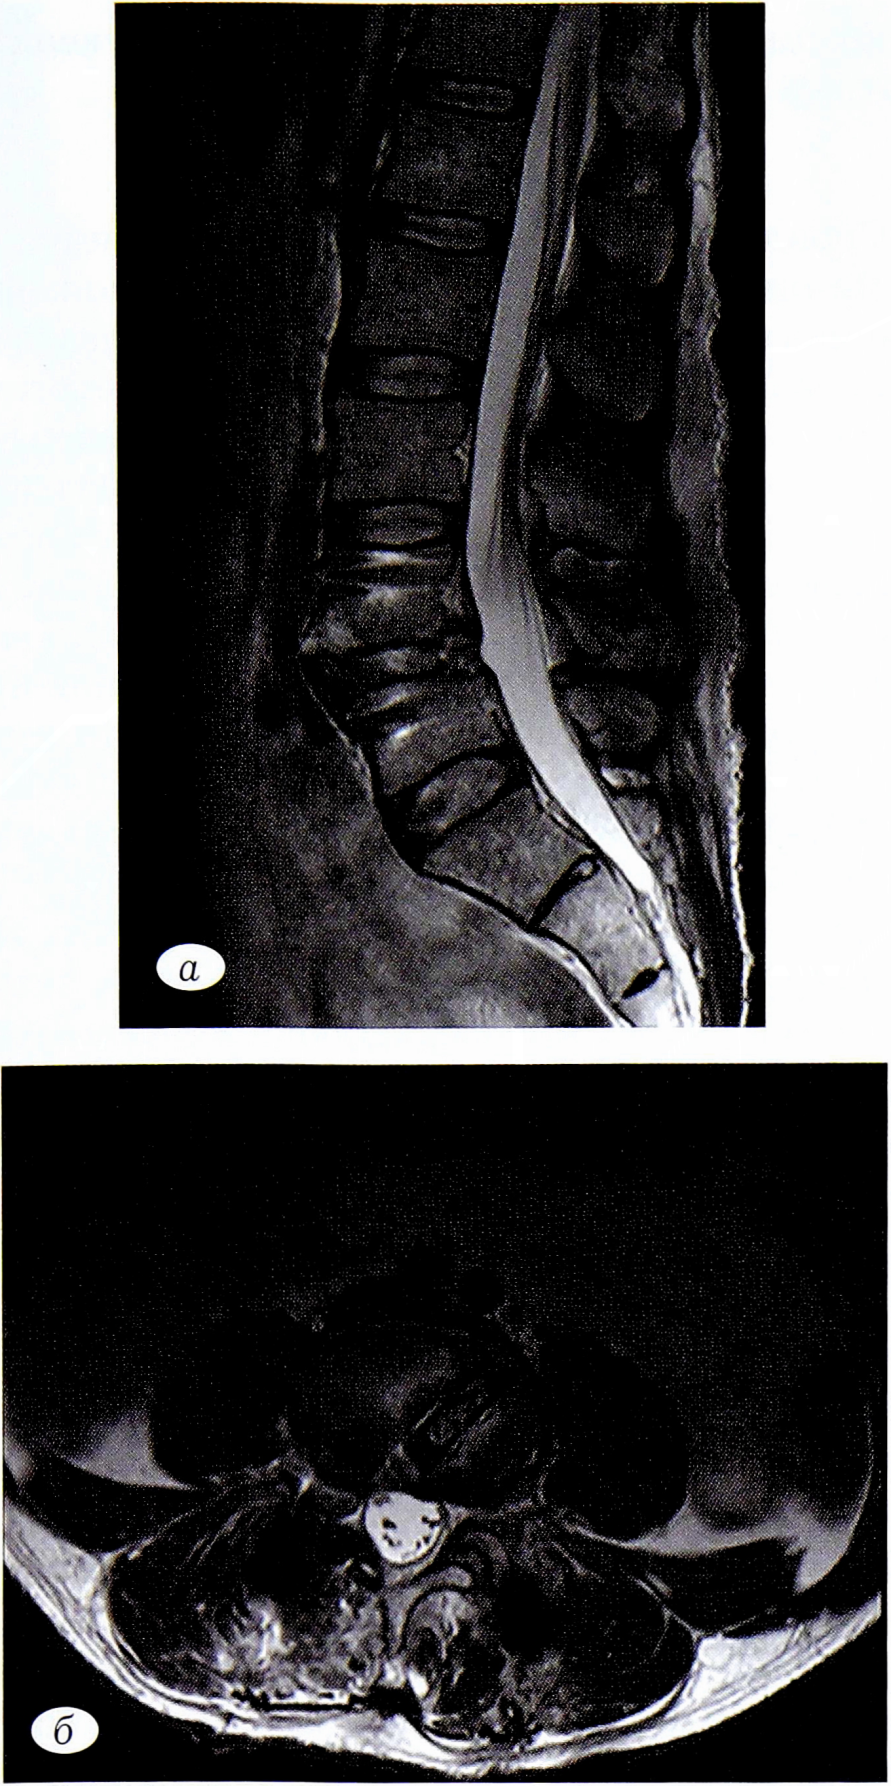

Данные магнитно-резонансной томографии (МРТ) поясничного отдела позвоночника (рис. 1, а, б): антеспондилолистез позвонка LIV II стадии, фораминальный стеноз на уровне LIV-LV с двух сторон.

Рис. 1. Предоперационные снимки МРТ поясничного отдела позвоночника пациента Ш. Определяется патологическое смещение в сегменте LIV-LV с двухсторонним фораминальным стенозированием: а — Т2-ВИ, сагиттальная проекция; б — Т2-ВИ аксиальная проекция на уровне межтелового промежутка LIV-LV.

Fig. 1. Preoperative MRI of the lumbar spine PAsh the patient is a pathological shift in the segment of LIV-LV with bilateral foraminal stenosis a and T2-Wi, sagittal projection; b — T2-VI axial projection at the level of the interbody interval LIV-LV.